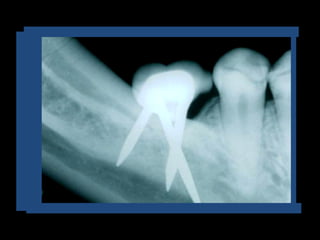

Rx Intraoral: Técnica De Cono Largo

• Altura de hueso disponible

• Relación con estructuras

anatómicas

• Amplitud

• Relación con piezas vecinas

• Presencia de patologías y-o

cuerpos extraños

• Traveculado óseo

Rx Periapical

• Es el método más

importante para los

controles postoperatorios

Controlan

fundamentalmente:

Asentamiento y

Ajuste protético

Estabilidad ósea

periimplante

Altura de Hueso Disponible: Relación con

estructuras anatómicas nobles

Es la altura de hueso que va desde la cresta alveolar hasta

1,5 o 2 mm de las estructuras anatómicas a preservar

Rx Intraoral: TécnicaDe Cono Largo • Altura de hueso disponible • Relación con estructuras anatómicas • Amplitud • Relación con piezas vecinas • Presencia de patologías y-o cuerpos extraños • Traveculado óseo

Rx Periapical • Esel método más importante para los controles postoperatorios Controlan fundamentalmente: Asentamiento y Ajuste protético Estabilidad ósea periimplante

Rx Periapical Altura deHueso Disponible: Relación con estructuras anatómicas nobles Es la altura de hueso que va desde la cresta alveolar hasta 1,5 o 2 mm de las estructuras anatómicas a preservar